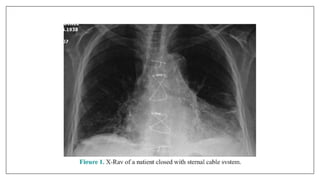

Surgical steel

• Used in sternotomy wounds closure, spine fixation etc